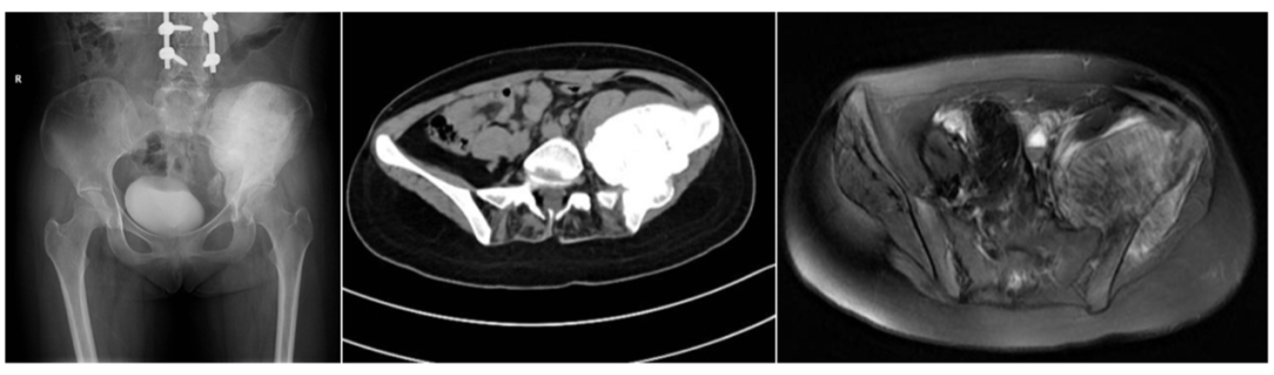

图:新辅助化疗后骨盆X线、CT和MR:左侧髂骨翼的肿瘤未见明显缩小,肿瘤内钙化明显增加,边界清晰。